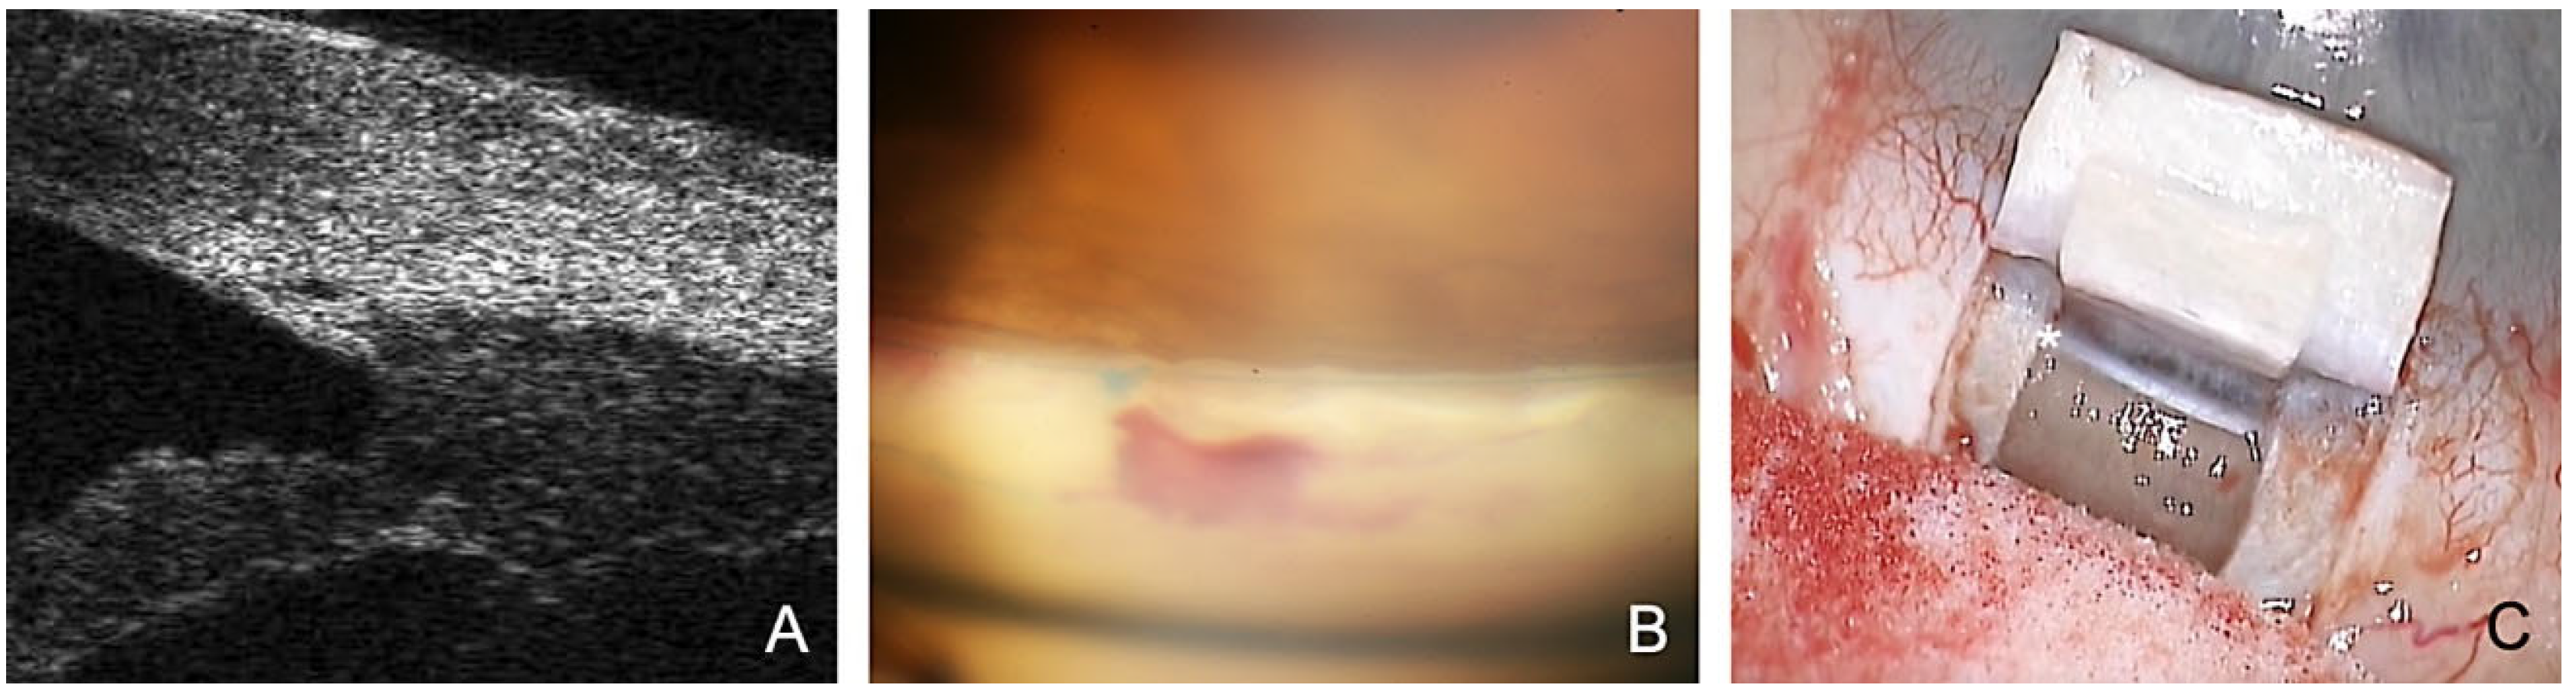

- The SC is probed using a microcatheter (iTrack 250, Ellex Inc., Eden Prairie, MN, USA) for dilatation of the ostia and lumen of SC, and the adjacent collector channels using a viscoelastic. This effect dilates the canal to almost triple its original size, making it easily visible in the ultrasound biomicroscope (UBM) 50 MHz (Figure 1A).